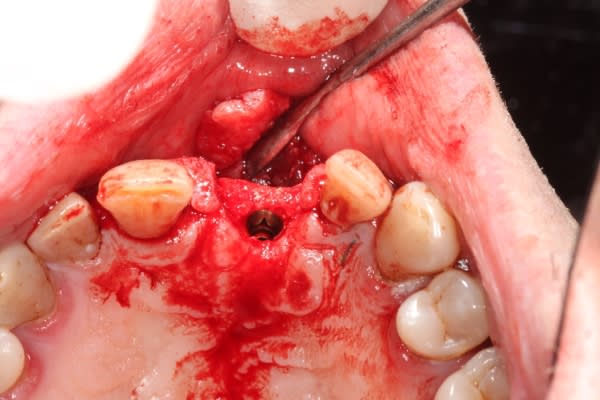

Extraction implantation immédiate mais il y a au moins 7 spires à nue... (photo 1, 2)

dans cette technique un pilier de 2mm de haut est vissé sur l'implant, ce pilier contient un orifice qui permet de transfixer la barre (photo 3,4)